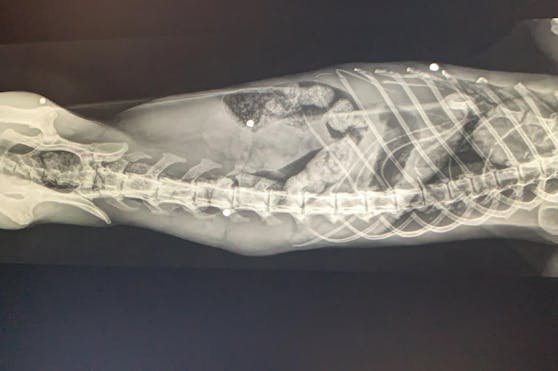

In einem Straßengraben in Rohrbach lag gestern ein blinder, alter, roter Kater in verheerendem Zustand. Tierschützer fanden den kleine Kerl und gaben ihn im Tierparadies Schabenreith in Steinbach ab. Dort wurde im Zuge einer Untersuchung erst das erschreckende Ausmaß seiner Verletzungen auf den Röngten-Bildern sichtbar. Offenbar wurde er mit einer Jagdflinte beschossen, denn sein kleiner Körper war von den Schrotkugeln nahezu durchsiebt und auch sein Brustbein ist gebrochen.

Die Nacht von gestern auf heute hat "Tizian" fürs Erste überstanden, obwohl es extrem kritisch aussah. Die Entfernung der Schrotkugeln ist leider nicht möglich, da sie sich offenbar schon länger in seinem Körper befinden. Derzeit bekommt er Injektionen zur Stabilisierung seines Kreislaufes. Das Ehepaar Hofner-Foltin tut sein Möglichstes um dem roten Kater einen angenehmen Lebensabend zu bereiten.